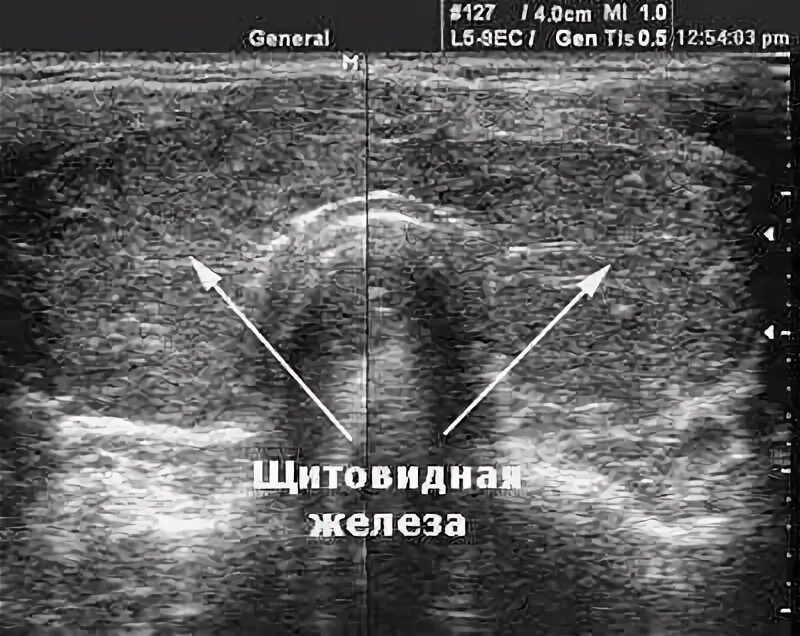

Диффузные изменения щитовидной железы на узи